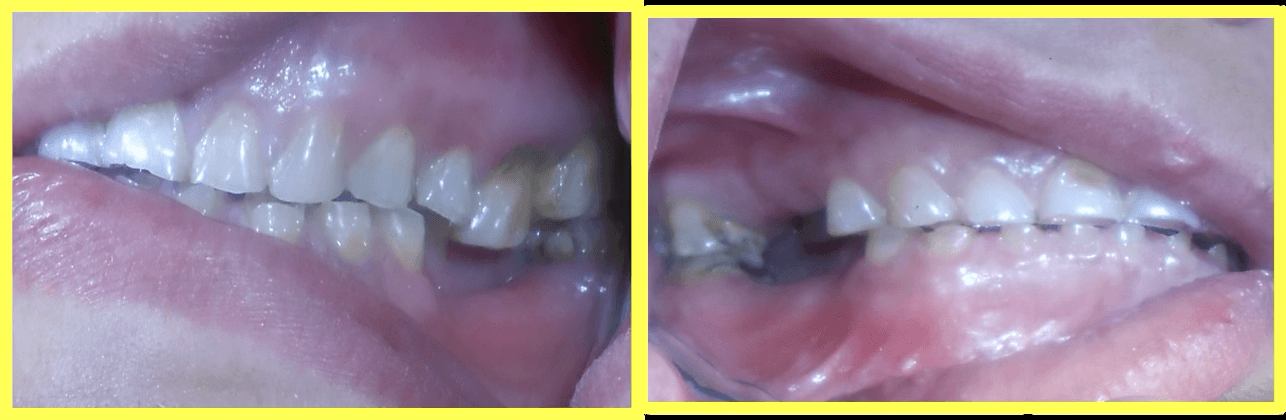

Initial condition

A 57-year-old female patient visited our dental center complaining of multiple missing and attrited teeth. On examination, patient had missing teeth 25, 26, 35, 36, 45 & 46 with grade 3 attrition. Treatment included impression-based muscle deprogrammer, Dio implants placement, PFM crowns for remaining attrited teeth, and delayed implant loading after 3 months.

Comprehensive oral examination with OPG X-ray. Patient presented with multiple missing teeth (25, 26, 35, 36, 45, 46) and severe attrition on remaining teeth. Muscle deprogrammer was fabricated and delivered.